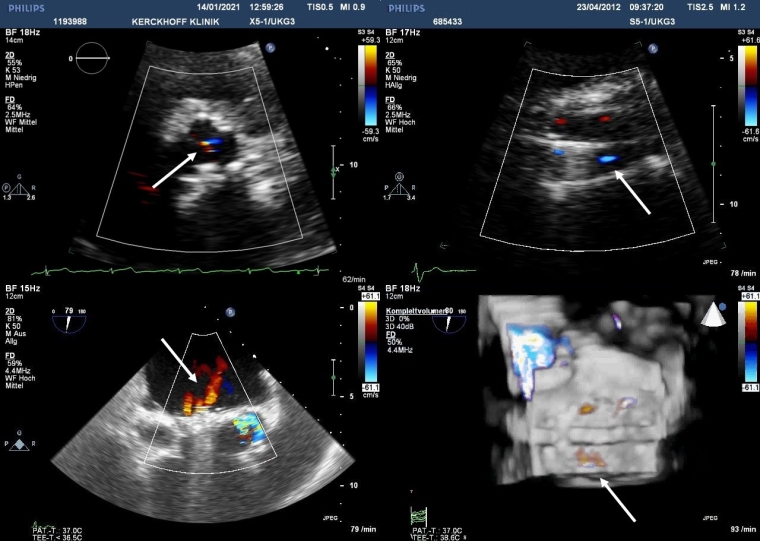

Detection and grading of prosthesis regurgitation involve several Doppler echocardiographic parameters and follow the same principles and methods used for quantitation of native valvular regurgitation [9-11]. However, they are more challenging, particularly in mechanical prostheses because of shielding and reverberations and the presence of multiple and eccentric jets. In BPVs, trivial to mild central valvular regurgitation on colour Doppler may be a normal finding due to minimal leaflet retraction provoked during implantation (Figure 1).

Figure 1. Colour flow Doppler images of physiological regurgitation in aortic prosthetic valves by transthoracic echocardiography (top) and mitral prosthetic valves by 2D and 3D transoesophageal echocardiography (bottom).

Trivial to mild valvular aortic regurgitation in a normally functioning BPV with the jet originating at the central coaptation point of all 3 leaflets (top left). Minor built-in regurgitation with 4 small and symmetrical jets in a mechanical bileaflet aortic valve (top right). A mechanical bileaflet mitral valve in closed position showing several regurgitant “washing jets” in systole in 2D imaging (bottom left). The same image from the atrial side in a 3D perspective obtained with multiple-beat acquisition (bottom right).

Minor, physiologic regurgitation is also inherent to all mechanical valves. First, a small amount of closing volume triggered by the backward motion of the occluder may be visible. Second, all mechanical valves with the exception of caged ball valves (no longer implanted) have trivial to mild transvalvular regurgitation at the edges of the leaflets. This “built-in” regurgitation theoretically prevents blood stasis and thrombus formation using a washing effect (Figure 1). This normal leakage backflow consists of one (Medtronic-Hall valve) or more (bileaflet valves) narrow and symmetrical jets inside the sewing ring and should be distinguished from aberrant paravalvular flow external to the sewing ring. Although periprosthetic regurgitation is abnormal, small single or multiple jets are not uncommon because annular calcification or fibrotic scar may lead to incomplete apposition of the sewing ring against the annulus. Technical factors during the surgical procedure and suture disruption from mechanical causes at a later point in time may also play a role. Finally, new paravalvular aberrant regurgitation may also be due to infective endocarditis.